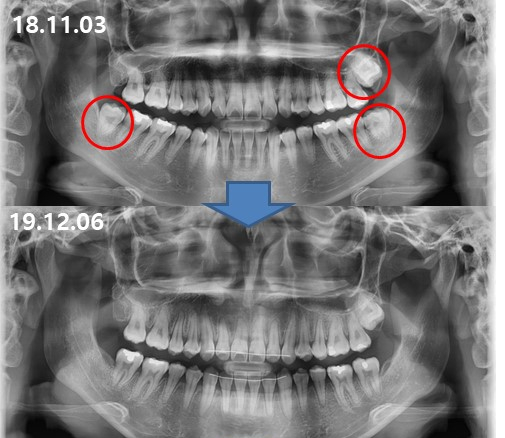

ÁÖ°ÆÅÎÀ» ÁÖ¼Ò·Î ³»¿øÇÑ

15¼¼ ¿©¼º ºÐÀÔ´Ï´Ù.

À§¾Æ·¡ Æø°æµµ ¸ÂÁö ¾Ê°í

¾Æ·¡ Ä¡¾Æ°¡ À§ Ä¡¾Æ º¸´Ù

4mm ÀÌ»ó

¾ÕÀ¸·Î ³ª¿Â °ÍÀ» º¼ ¼ö ÀÖ½À´Ï´Ù.

°á°ú´Â

¾Æ·¡¿Í °°Àº ¿òÁ÷ÀÓÀ¸·Î

½ÉÇÑ ÁÖ°ÆÅÎÀÌ¿´Áö¸¸

ºñ¼ö¼ú ÁÖ°ÆÅÎ ±³Á¤Ä¡·á¸¦ ÅëÇØ¼­

°Ç°­ÇÏ°í ¾ÈÀüÇϰÔ

13°³¿ù ¸¸¿¡

Ä¡·á¸¦ ¿Ï·á ÇÏ¿´½À´Ï´Ù.

¿·¾ó±¼ ¿¢½º·¹ÀÌ¿¡¼­´Â

ÀÌ·± º¯È­°¡ ÀϾ½À´Ï´Ù.

ºñ¼ö¼ú ÁÖ°ÆÅÎ ±³Á¤Ä¡·á¸¦ ÇÏ´Â

13°³¿ù µ¿¾ÈÀÇ ÁÖ¿ä º¯È­ÀÔ´Ï´Ù.

Ä¡·á ½ÃÀÛ 7°³¿ù ÈÄ¿¡

Á¤»ó±³ÇÕÀ¸·Î ¹Ù²ï ÈÄ

À¯Áö, ¾ÈÁ¤À» º¸´Ù°¡

13°³¿ù¿¡ Ä¡·á¸¦ ³¡³Â½À´Ï´Ù.